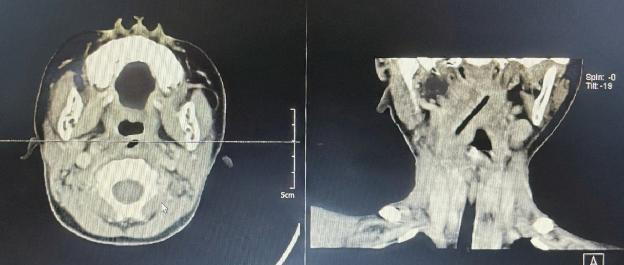

| Phim chụp đũa gỗ trong cổ bệnh nhi |

Tại đây, sau khi được làm các xét nghiệm, chụp chiếu, các bác sĩ chẩn đoán bệnh nhi có áp xe vùng cổ phải nghi ngờ có dị vật bỏ quên sau chấn thương.

ThS.BS Trần Hữu Thắng,Trưởng Khoa Cấp cứu, Bệnh viện Tai Mũi Họng Trung ương, khối sưng vùng cổ có thể là do một mảnh dị vật bị bỏ quên bên trong gây ra, nhưng khi hội chẩn với các chuyên gia về X-quang thì thấy hình ảnh không rõ ràng và vị trí dị vật không cố định nên rất khó cho việc phẫu thuật.